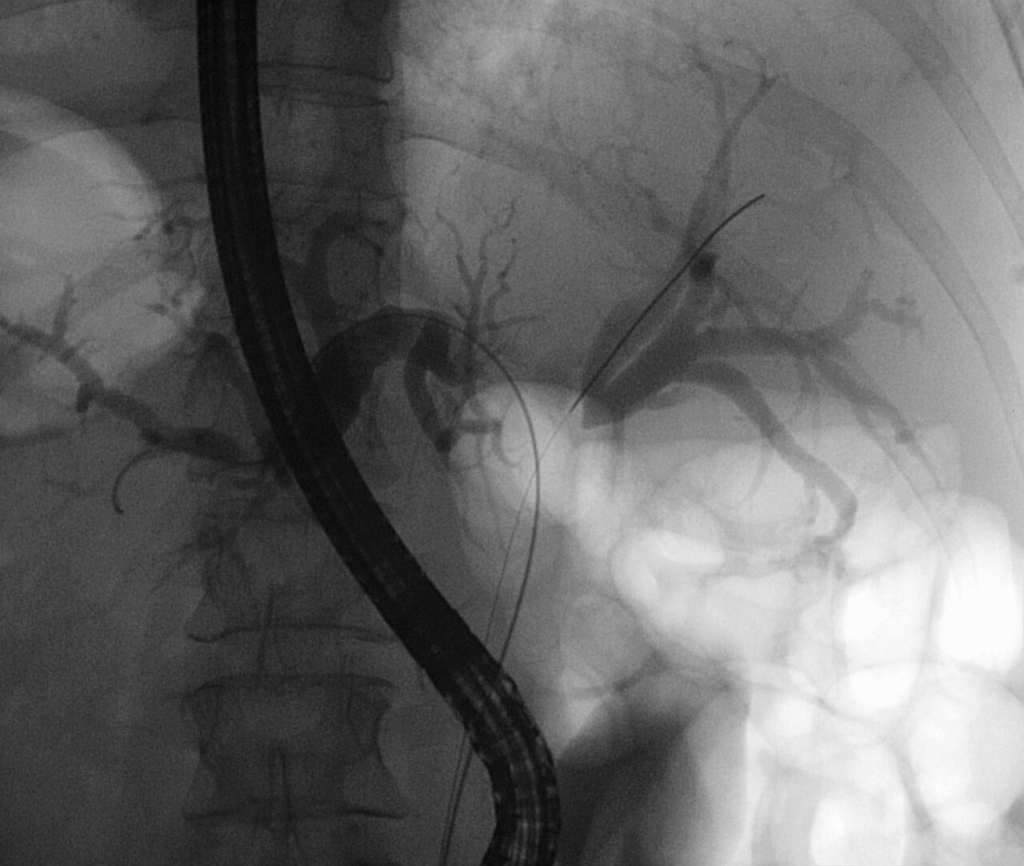

- Colangiopancreatografia Retrograda Endoscopica (ERCP) e Colangiografia Percutanea Transepatica (PTC): queste tecniche invasive hanno un duplice ruolo. Permettono una visualizzazione diretta dell’albero biliare per valutare l’estensione duttale del tumore e consentono il prelievo di campioni tissutali (brushing citologico, biopsia endobiliare). Inoltre, offrono la possibilità di un drenaggio biliare terapeutico tramite il posizionamento di stent. È importante sottolineare che una biopsia o un brushing negativo non esclude la diagnosi di colangiocarcinoma, data la natura sclerosante di molti di questi tumori.